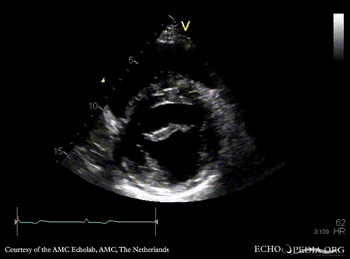

| PLAX: dilated aortic root, redundant mitral valve leaflets

PLAX: dilated aortic root